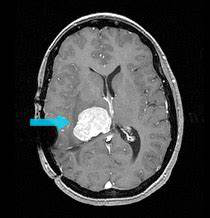

脑室内脑膜瘤相对少见,占全部脑膜瘤的1%~2%。脑室内脑膜瘤的一例记录可能是1854年由Shaw提出的。他在侧脑室三角区发现了一个囊状的纤维性肿瘤。1881年,麦克道尔进行了左三角肿瘤手术。1938年,Cushing和Eisenhardt一次描述了一例位于三脑室的脑膜瘤。从那时起,在文献中有许多关于脑室内脑膜瘤病例的报告,讨论了在处理这些可怕的手术损伤时可能遇到的问题和困难。迄今为止,大约有600例脑膜瘤被报告。其中约80%位于侧脑室,15%位于三脑室,5%位于四脑室。

与大多数其他脑膜瘤一样,脑室内脑膜瘤也以女性为主。这些脑膜瘤有时被认为是神经纤维瘤病2(NF2)的一部分,也与多发性脑膜瘤有关。患者可能没有任何明显的神经症状,即使肿瘤已经达到较大的尺寸。由于生长方式的性质,有些肿瘤可能是偶然发现的。在这种情况下,考虑到生长缓慢和手术中可能遇到的困难,保守的观察可能是一个可行的治疗选择。肿瘤的高血供很少与肿瘤内出血和急性症状有关。

脑室内脑膜瘤的手术挑战了神经外科医生的手术技巧,是因为更深的肿瘤位置以及邻近于脑室重要结构而存在较大的挑战。手术经验和完全的解剖知识是至关重要的切除这些病变。虽然成功的手术切除是与正常生活相适应的,但在计划方法或实施手术中的任何错误都可能导致神经功能缺损甚至死亡。在尝试手术之前,需要对三角区的解剖、动脉和静脉模式以及与视觉通路和大脑半球优势的关系进行评估。当计划手术时,手术需针对根治性或全肿瘤切除,因为不完全或部分肿瘤切除可能导致肿瘤出血相关问题。脑室内脑膜瘤手术计划的相关问题包括评估肿瘤的大小、一致性、血管分布、供血血管的位置和生长方向。决定手术成功的基本原则包括:尽早获得血液供应,在切除大量肿瘤的同时尽量减少对大脑的牵拉,以及了解周围解剖结构的功能。在手术早期,通过半脑间入路和暴露肿瘤内侧部分来控制供血血管似乎是一种合理的手术选择。